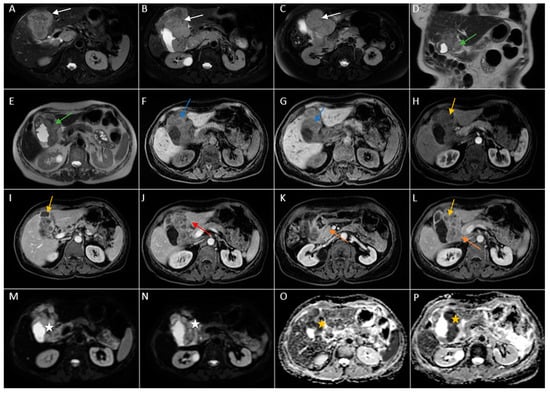

Abdominal MRI was performed (Figure 10).

Figure 10. Abdominal MRI images vividly illustrating epithelial gallbladder carcinoma. (AC). Axial T2-weighted FS showing inhomogeneous moderate hypointense heterogeneous tumoral parietal mass surrounding the gallbladder (white arrow). (D,E). Coronal and axial T2-weighted images showing hypointense heterogeneous tumoral gallbladder mass (green arrow). (F,G). Axial T1-weighted illustrating iso-hypointense tumoral mass (blue arrow). (HL). Axial contrast-enhanced T1-weighted image (arterial phase followed by venous phase) showing a heterogeneous enhancement of the gallbladder mass with areas of necrosis (yellow arrows). The mass invades the adjacent liver ((J), red arrow) and duodenum II ((K,L), orange arrows). (M,N). Diffusion-weighted imaging (DWI B800) showing bright signal of the large gallbladder mass (white stars). (O,P). On ADC map, the large gallbladder mass is dark, illustrating diffusion restriction (yellow stars).